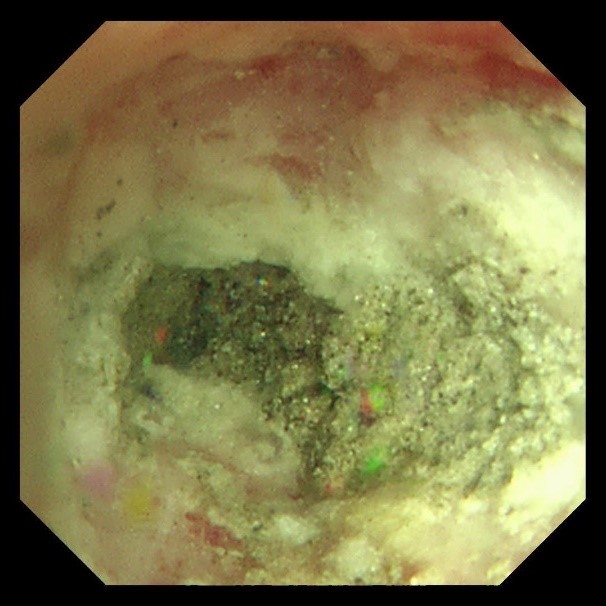

首次支气管镜清除手术:解决大块异物阻塞。因患者颈部有损伤,未行硬镜置入,在麻醉手术科的密切配合下,为患者经口插入8.5号气管插管,接呼吸机辅助通气,建立稳定的呼吸通道。随后,气管镜顺利进镜,发现气管及左主支气管内充满泥沙样分泌物、黄脓痰及块状异物。随后,实行精准操作:用吸引器清除泥沙样物质及黄脓痰;使用活检钳分次取出左下叶大块石状异物,并配合取石网篮清理;刷检带出细小碎石,并进行多部位生理盐水灌洗,最大限度清除可见异物。

(超细支气管镜见左下叶背段远端支气管泥沙样物质)